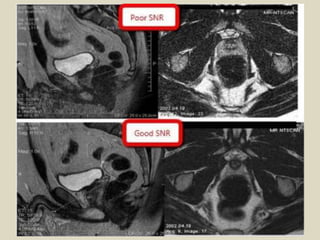

Magnetic resonance imaging (MRI) was discovered in 1947 by two physicists and the first clinical images were obtained in 1977. MRI uses strong magnetic fields between 1-9 Tesla to align hydrogen atoms in the body and radio waves to elicit signals to form images. The document provides a brief history of MRI and discusses magnetic fields, relaxation processes, and pulse sequences used to generate MRI images.